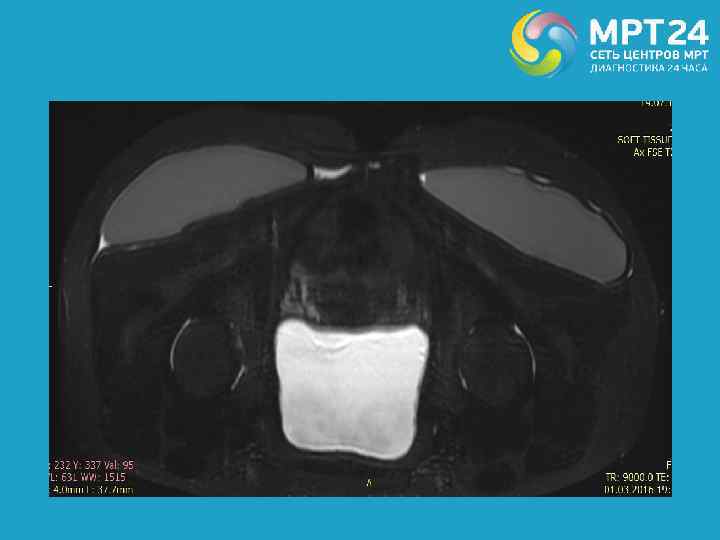

Собственное наблюдение. Женщина 40 лет, состояние после глютеопластики, без признаков нарушения целостности имплантов.